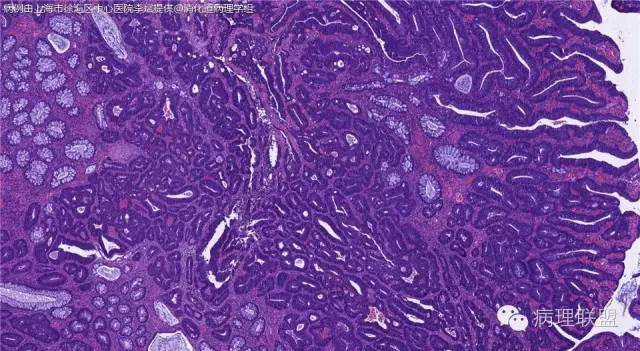

男,72岁,距肛门口30cm息肉。大体:灰白结节1.5*1*0.8cm拟发管状腺瘤并部分区高级别,请各位老师指导!(病例由上海市徐汇区中心医院 李斌 提供,致谢!)

这一例有两种不同看法,按WHO标准,为高级别,按实际工作,要发粘膜内癌。WHO第三版与第四版均提出,侵犯至粘膜下层才能诊断为癌,声称结直肠粘膜内没有淋巴管,发生转移的概率较小,但是粘膜内有血管,肿瘤侵出粘膜腺体基膜以外,就能侵犯血管,照样可以发生血道转移。文献报告与我们的工作实践,发现腺瘤、高级别(没有侵出基膜)的患者,同样有发生血道转移。因此,我们废弃了这一条WHO标准(不是所有的WHO标准都是一定要执行的)。只要异型增生腺体呈毛刺状、迷芽状侵出粘膜腺体基膜,位于粘膜肌层以内,就发粘膜内癌。

@李斌 结肠腺瘤这例我认为已经有黏膜下浸润了,因为有些腺体间的间质已经不是固有膜间质而是促结缔组织增生反应的间质了。但即使有浸润癌,如果息肉完整摘除、癌成分分化好、没有脉管瘤栓、浸润癌距切缘大于1mm(日本标准还要看浸润癌超出黏膜肌深度和肿瘤出芽情况),也不需要进一步治疗。所以,对于这类可能存在争议的病变,特别是息肉已经完整切除的病例,诊断的关注点就应该放在寻找需不需要进一步治疗的证据上了。@邓永键 2010版WHO在腺瘤部分的陈述中已经写出对于有局灶浸润性生长的病例也可以称黏膜内癌,他们在悄悄的让步。